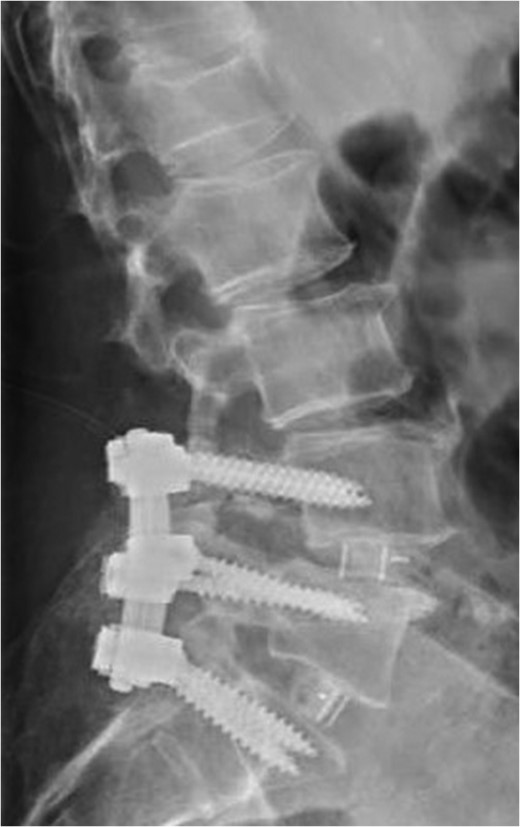

Standing neutral lateral lumbar radiograph obtained the day following the patient's L4–S1 revision decompression and posterior instrumented fusion with TLIF performed at each of these revised levels. A moderate correction of the prior L4-5 anterolisthesis was achieved and the patent's spine and construct appear stable.